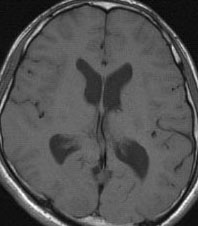

けいれん発作だけで発症した例

脳表のくも膜下腔がガドリニウム造影剤で白く造影されます。これはくも膜下腔ではなくて軟膜のメラノーシスが増強されているものです。髄液播種とは髄腔の見え方が少し違います。